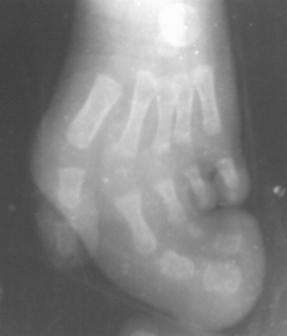

Парциальный гигантизм

Ребенок 2 года. Диагноз < Парциальный гигантизм <. 2 и 3 пальцы стопы увеличены в размеры за счет допольнительных пальцевых костей и п/к жировой клетчатки.